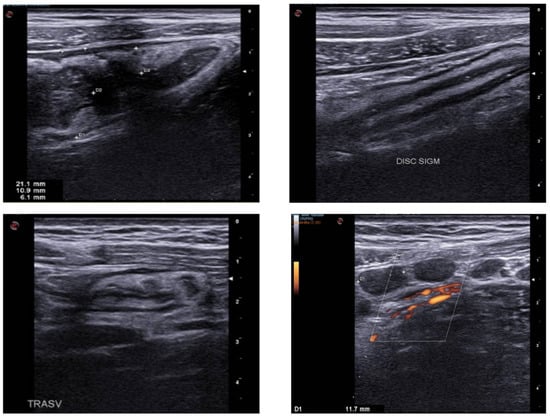

5. Acute Diverticulitis

4. Acute Appendicitis